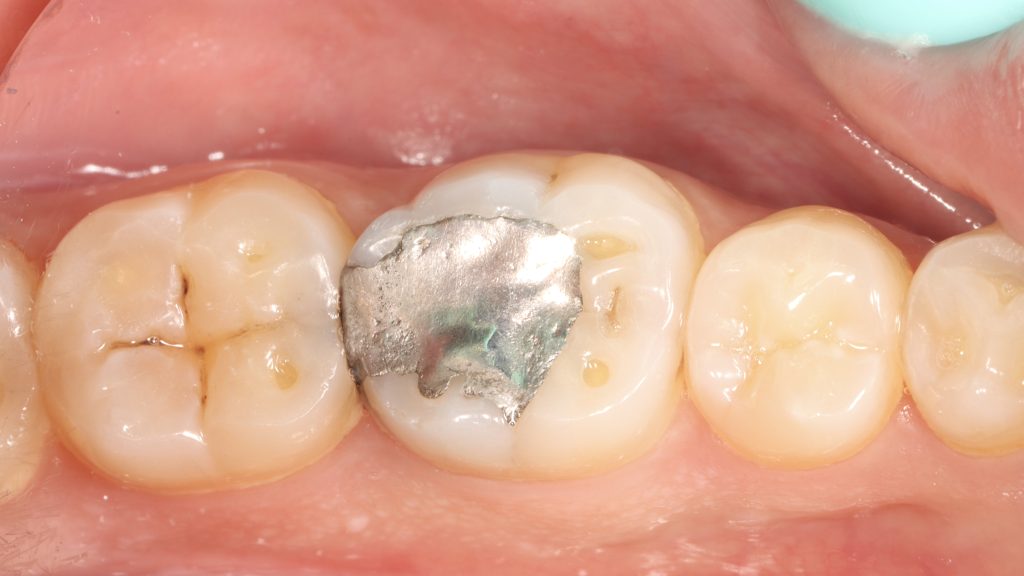

1.This patient presented with defective old amalgam proximal restoration with food impaction and difficulty in flossing , so the decision was to replace it with more healthy , functional and esthetic one.

2.Before isolation, pre-wedging step for separation between teeth and protection the papilla and just breaking the contact to insert sheet dam without tearing.

3.after rubber dam isolation and wedge placement, a good vision obtained to prepare a slot cavity in tooth number 31 and amalgam removal from tooth number 30.